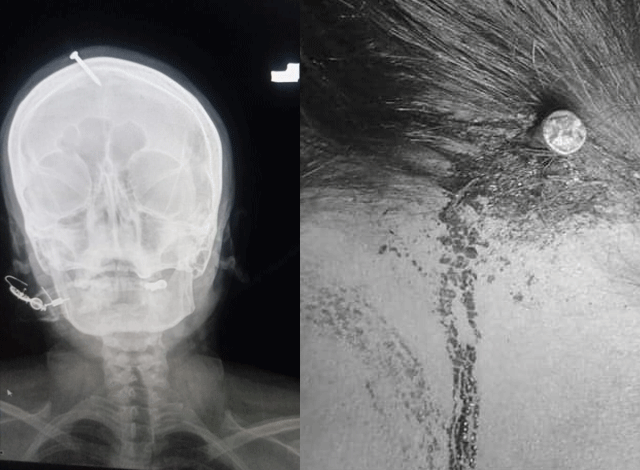

پشاور: پشاور ۾ هڪ جعلي پير پٽ جي خواهش رکندڙ ڳورهاري عورت جي مٿي ۾ ڪوڪو ٺوڪي ڇڏيو. پشاور ۾ پٽ جي خواهش رکندڙ هڪ عورت کي جعلي پير ڏٽو ڏئي مٿي ۾ ڪوڪو ٺوڪي ڇڏيو، متاثر عورت کي زخمي حالت ۾ ليڊي ريڊنگ اسپتال پهچايو ويو. اسپتال جي نيورو سرجن ڊاڪٽر حيدر موجب ڪوڪو ٺوڪجڻ سبب ڳورهاري عورت کي مٿي ۾ سخت ڌڪ لڳو پر سرجري کانپوءِ ڪوڪو ڪڍيو ويو آهي. ڊاڪٽر ٻڌايو ته جعلي پير پٽ جي پيدائش جو چئي عورت جي مٿي ۾ ڪوڪو ٺوڪي ڇڏيو، متاثر عورت جي مڙس کي ڌيئر پسند نه هيون.